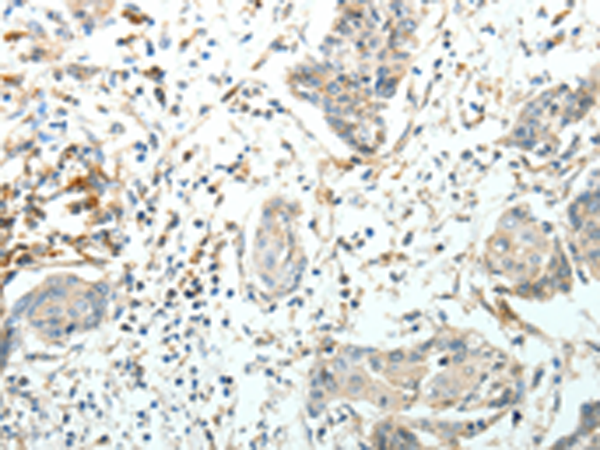

分类: 科研抗体货号: P11178别名: AR; ADR; ALR2; ALDR1应用: WB,IHC反应种属: Human